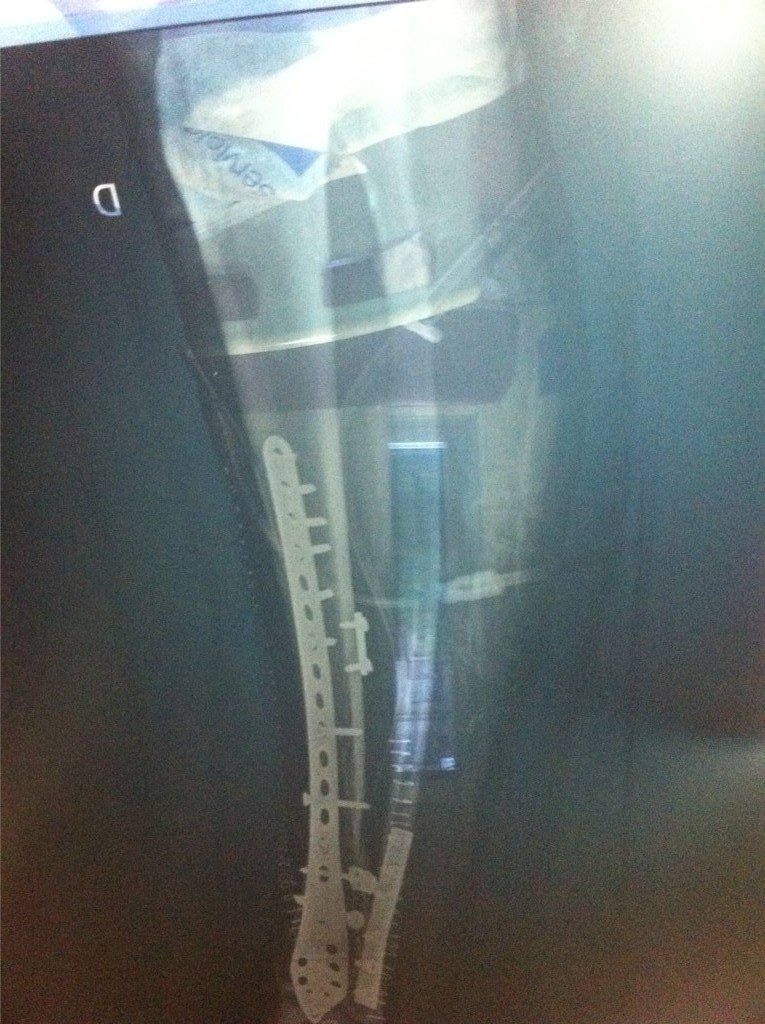

Tegnap az USP San José Hospital sebészeti osztályán megoperálták Julian Simont, aki a hétvégi Moto2 futamon sérült meg. A Kenan Sofuogluval való ütközés megviselte a lábát – biztos, hogy több futamot ki kell hagynia. Olasz sajtóértesülések szerint csapata talán Talmácsi Gábort kérné fel a lábadozó motoros helyettesítésére.